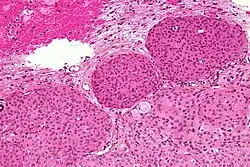

- A woven architectural pattern

- Psammoma bodies (spheroid calcifications)

- Syncytial cells (having indistinct cell membranes) with eosinophilic (pink) cytoplasms

- Round uniform nuclei

- Whorls (concentric cell arrangements)[16]

Histologically, meningioma cells are relatively uniform, with a tendency to encircle one another, forming whorls and psammoma bodies (laminated calcific concretions).[19] As such, they also have a tendency to calcify and are highly vascularized.

- ^ Image by Mikael Häggström, MD. Reference for typical findings: Chunyu Cai, M.D., Ph.D. "Meningioma". Pathology Outlines.